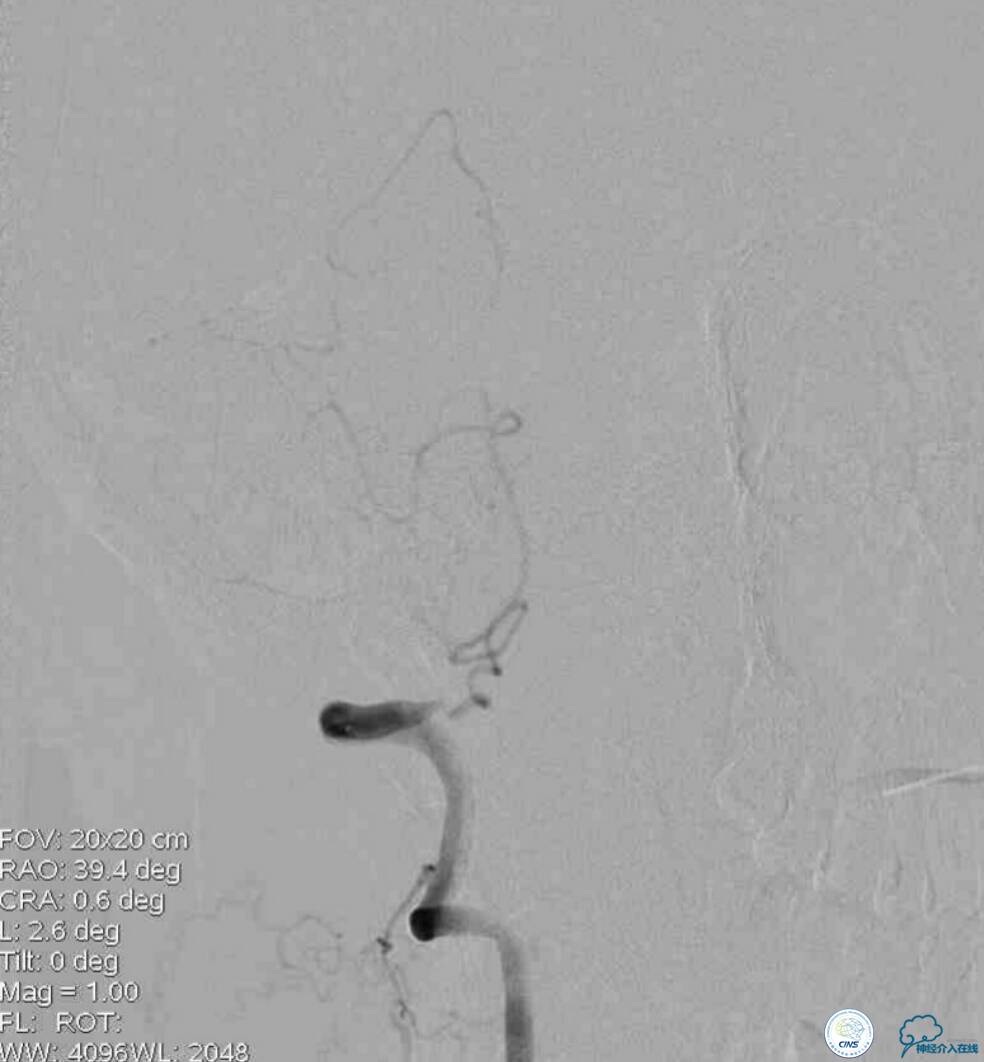

病后就诊当地医院,予以双抗+积极控制危险因素治疗,但症状持续无缓解,就诊期间核磁检查提示右延髓新近脑梗死,MRA示双椎及基底动脉显示欠佳(图1)。

同期行DSA提示右椎动脉V4段发出右PICA后未见顺行显影(图2),左椎动脉V4段-基底动脉汇合处重度狭窄(图3),前循环向后循环的未见明显代偿(图4)。